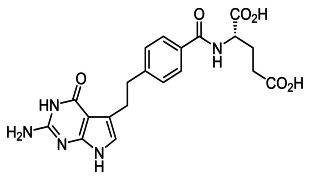

Product PEG-Free Shielding Lipids

Shielding lipids are key to keeping LNPs stable, long‑circulating, and efficient at delivering RNA or gene‑therapy payloads. As PEG‑based systems face growing concerns due to immunogenicity and accelerated clearance, new PEG‑free strategies are becoming essential for safer and more flexible nanoparticle de...